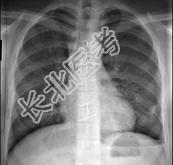

- 单项选择题18岁,男, 被人殴打后胸痛,请结合胸片选出最可能的诊断 ( )

A、血气胸

B、气胸

C、胸腔积液

D、肺气肿

E、肺挫伤